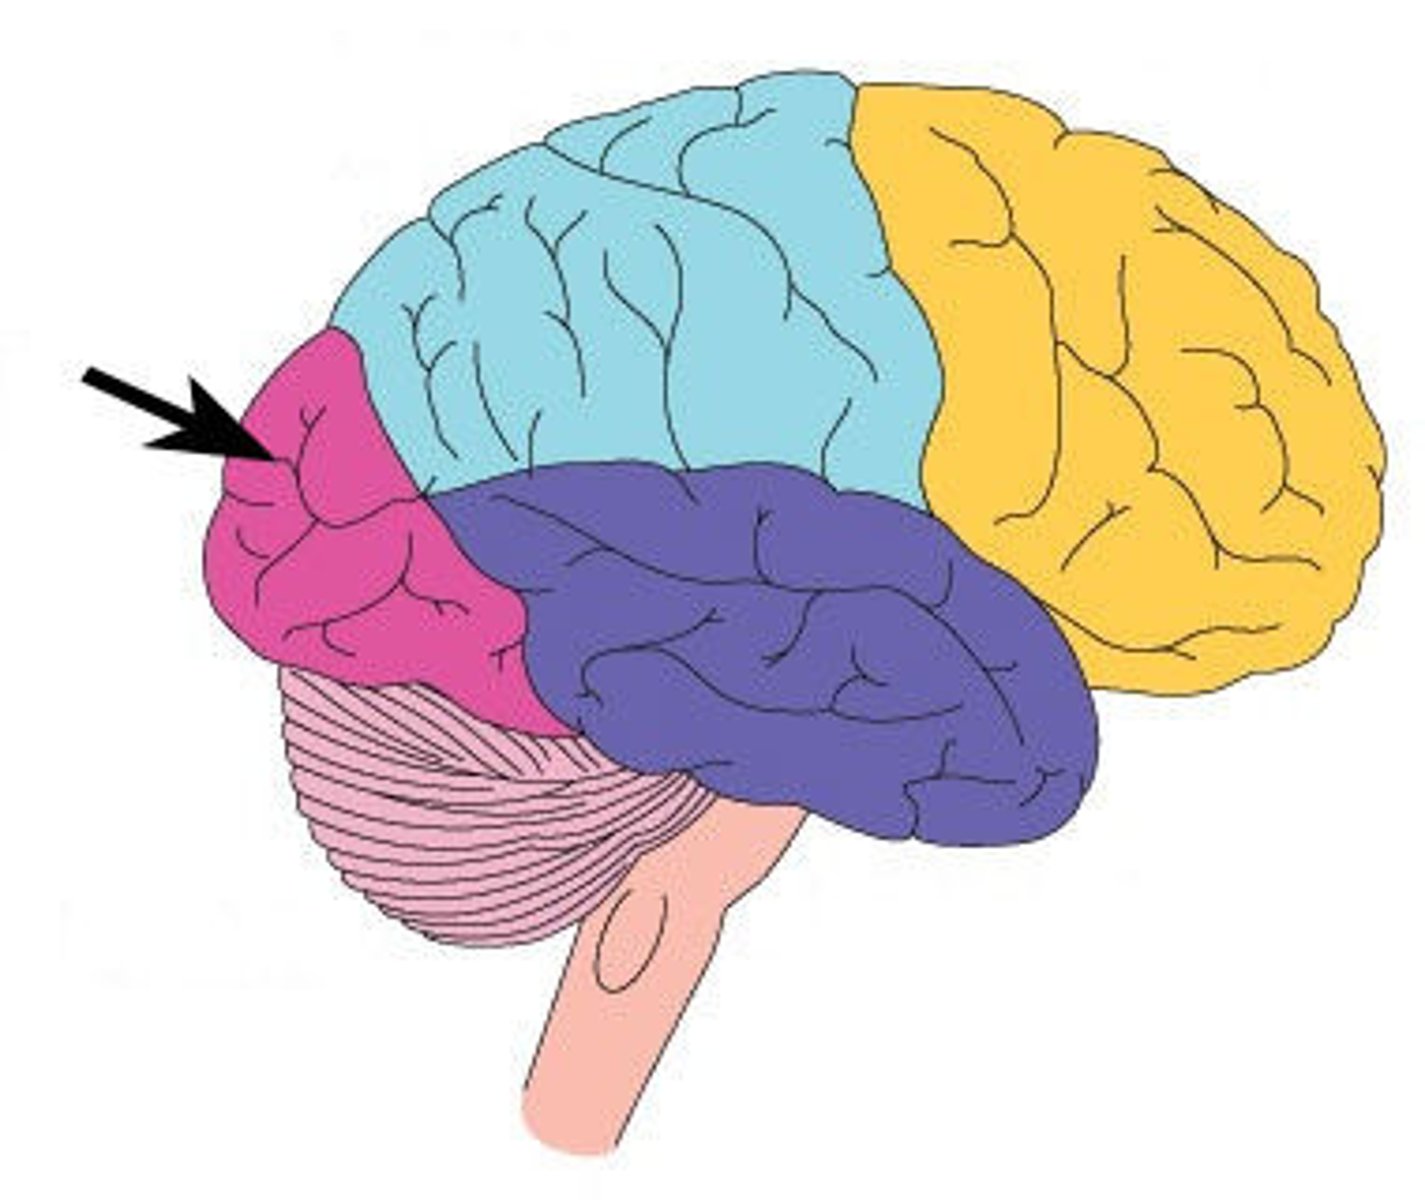

frontal lobe

Regions of the cerebrum involved in:

•Voluntary motor functions

•Motor control, concentration, verbal communication, decision making, planning, personality

parietal lobe

Region of the cerebrum that:

•receives and integrates general sensory information (shape, texture), taste and some visual processing

occipital lobe

•primary visual center of brain (vision and visual memories)

temporal lobe

Regions of the cerebrum that:

•contains areas for hearing, smell, learning, memory, and some aspects of vision and emotion

central sulcus

separates frontal and parietal lobes

lateral sulcus

Separates temporal lobe from parietal and frontal lobes